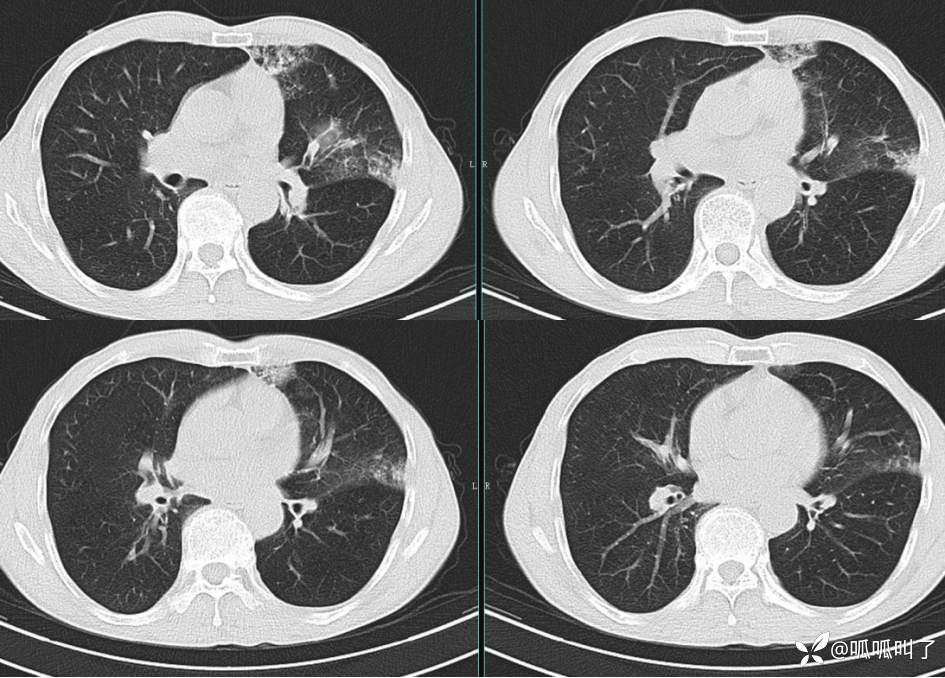

胸部CT平扫和增强: